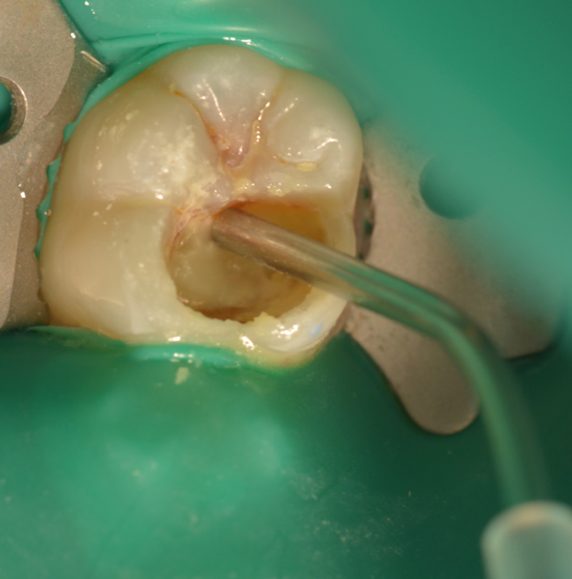

A female patient presented with sensitivity and occasional pain on stimulus in her lower left back tooth. On clinical examination deep carious lesion was present in her lower left first molar tooth (Fig.1). Tooth was non tender to percussion. Radiographic examination revealed deep lesion in close proximity to the pulp with no significant periapical changes (Fig. 2). Patient had a high caries index and therefore a bioactive restoration with Predicta Bulk was considered.

Fig. 1. Deep carious lesion in lower left first molar